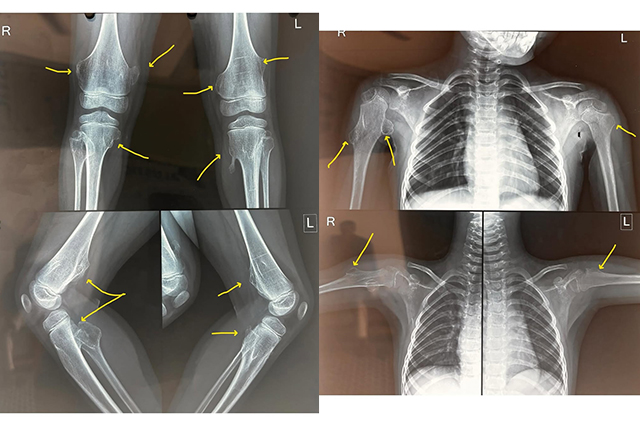

Multiple Hereditary Exostosis (MHE): Understanding a Rare Bone Disorder

🔍 What is Multiple Hereditary Exostosis (MHE)?

Multiple Hereditary Exostosis (a...